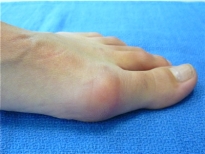

Exemple de correction par une ostéotomie en chevron du pied gauche:

AVANT:

APRÈS: